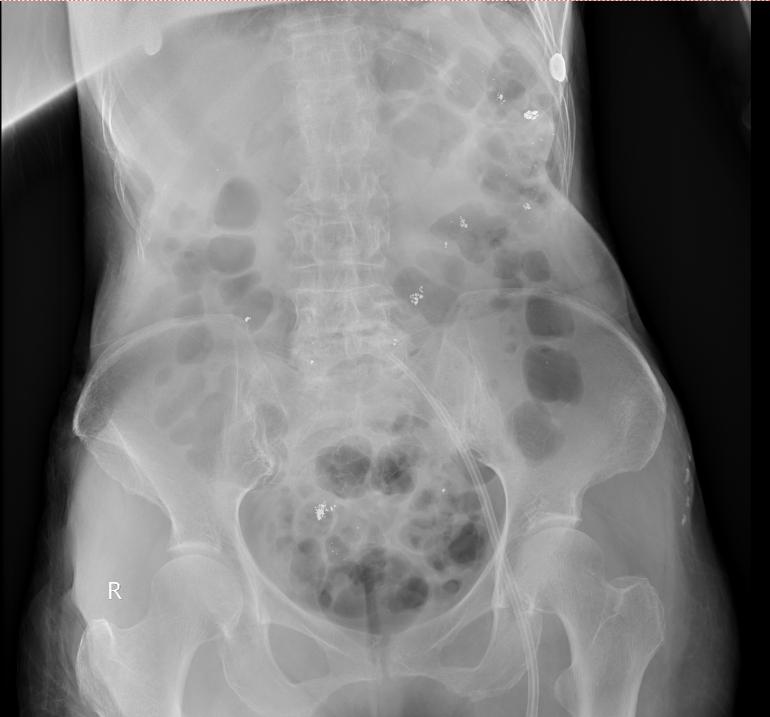

入院当天,姜阿婆尿汞浓度高达73465.47μg/L(肌酐校正),比正常值高1万8千多倍;反映肾功能的肌酐清除率仅有6.21ml/min,出现无尿,提示已存在肾功能衰竭;转氨酶、心肌酶升高,肝脏、心肌均出现了不同程度的损害。